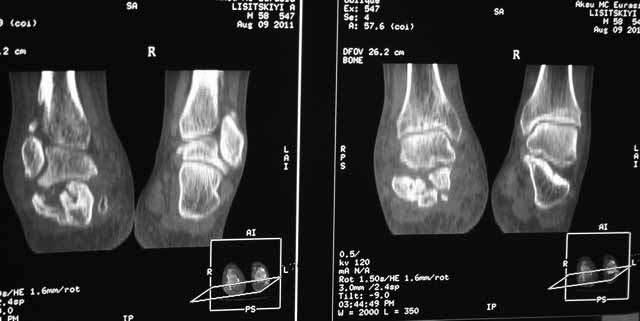

КТ перелома пяточной кости Пациент 60 лет с производственной травмой-закрытые переломы правой пяточной кости, тибиального плато слева поступил в феврале с.г. На 4 сутки выполнена открытая репозиция, остеосинтез внутрисуставного перелома голени, ручная репозиция пяточной кости. Через три месяца начал ходить с нагрузкой на обе ноги. Консолидация голени с полным восстановлением функции колена. Правая стопа умеренно отечна, продольно распластана, длительная ходьба вызывает боли и увеличение отека. Прошел несколько курсов ударно-волновой терапии, грязелечение, боли и отек уменьшились. В наших планах -оформление на ВТЭК, через год возможно выполнение подтаранного артродеза.Но после производства КТ в августе появились сомнения в консолидации перелома.Ранее у нас не было опыта КТ переломов стопы и сканы привели в замешательство.Прилагаю снимки со дня поступления, августовские пациентом не представлены.С благодарностью примем советы коллег.

Данное исследование сделано в неправильной позиции стопы, стопа находится под прямым углом. Но несмотря на это, здесь можно увидеть, что латеральная стенка смещена, фиброз между фрагментами и варусное смещение пятки.

Топография зависит от позиции пятки в пространстве и неправильное положение закрывает обзор нужных структур. Важными структурами в исследовании пятки является задняя фасетка, бугор и боковые стенки. Существует специальные рентгенснимки, показывающие импинджмент с лодыжкой, а также положение бугра. Для КТ стопу надо инклинировать под 30 градусов, иначе можно пропустить важные переломы.

Информация о правильном обследовании пяточной кости на КТ. Computer tomography of calcaneal fractures: Anatomy, pathology, and clinical relevance. Guyer BH, Levinsohn EM, Fredericksohn BE, et al: Am J Radiol 1985;145:911-919.